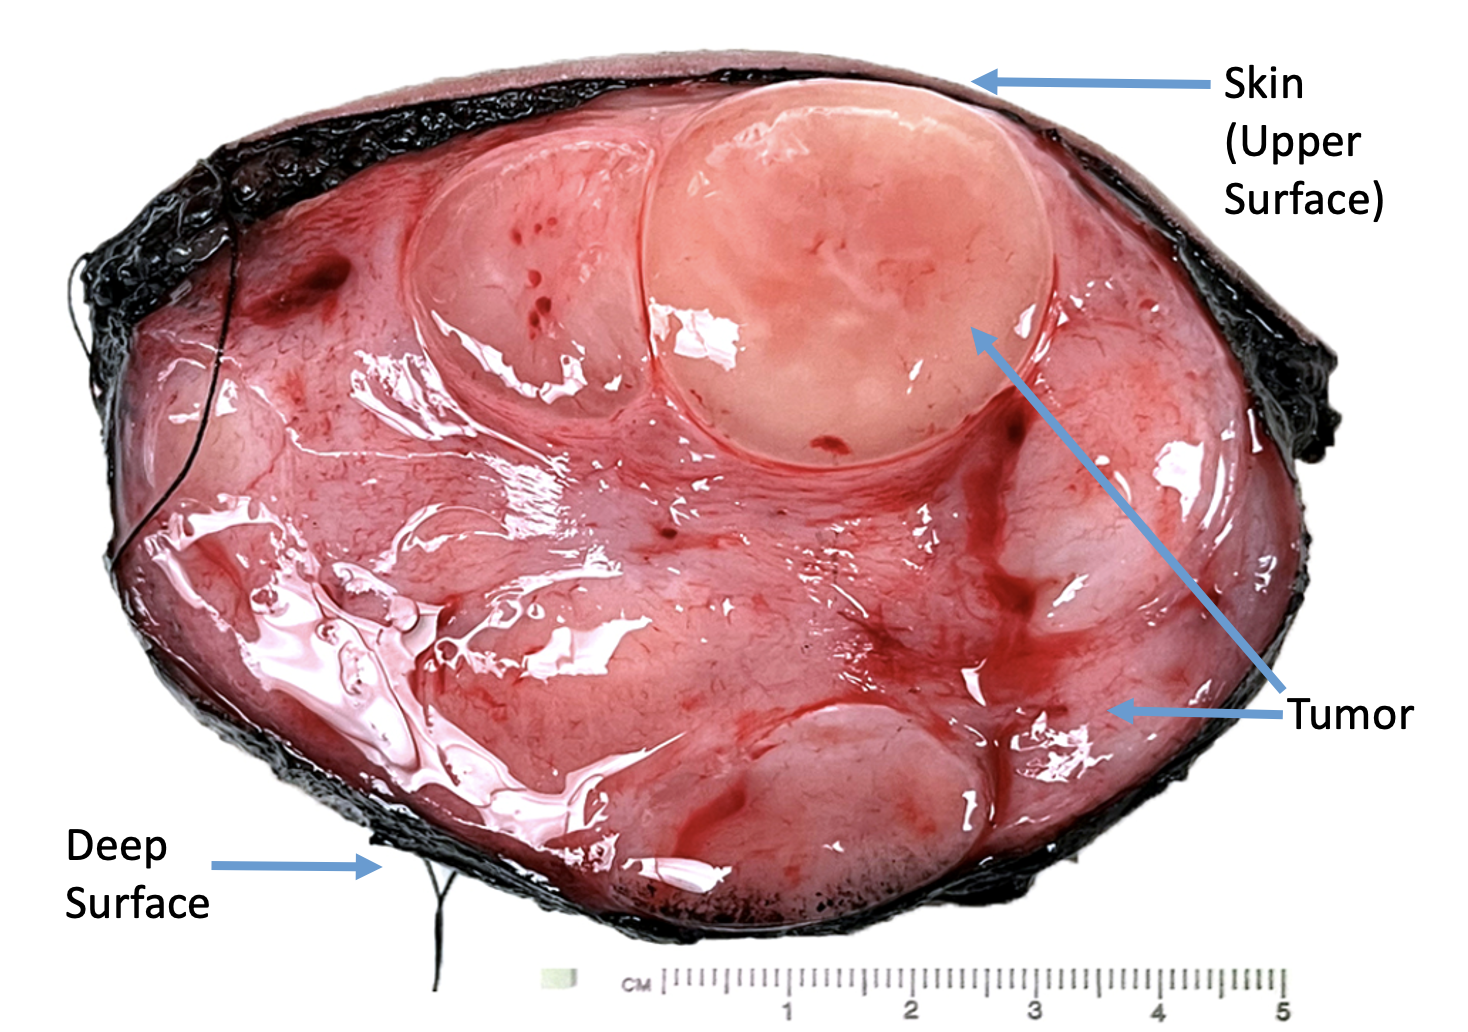

The mass was excised en-bloc and found to be well-circumscribed and not involving the muscle fascia (Figures 1C and 4). The surgery was uncomplicated. Pathology diagnosed mixed DFSP (Figure 5B) and GCF (Figure 5C) with no evidence of high-grade fibrosarcoma transformation. The tumor extended to the dermal, subcutaneous, and deep margins.

Figure 4. Pathology gross picture. Cut surface (skin upper) showing myxoid, and fleshy, fibrous lobulated and nodular circumscribed tumor in dermis and subcutaneous tissues.